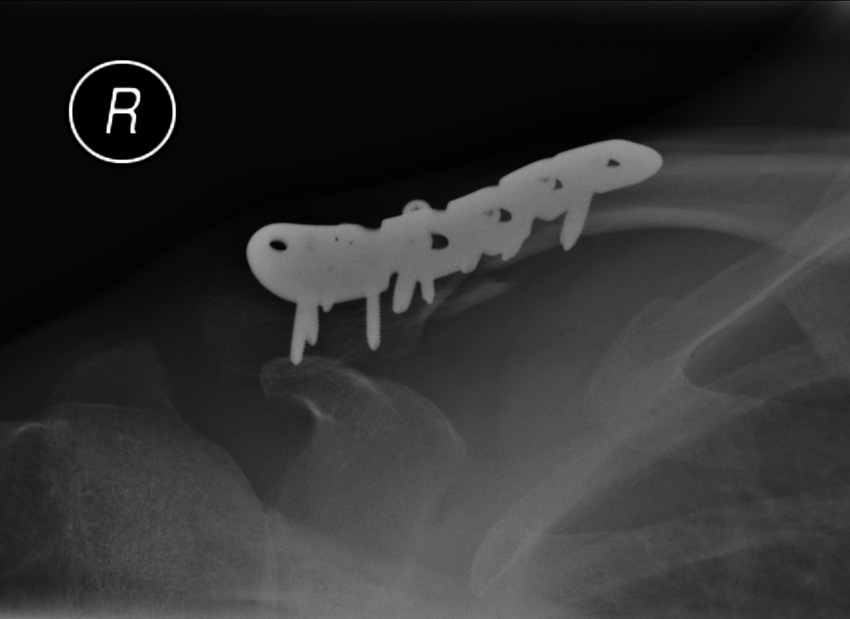

pinned hip

[URL= http://i239.photobucket.com/albums/ff167/LukeBurstow/3d825ec0-098c-4809-95fd-64cc9d960fcb_zps34dd21d4.jp g" target="_blank">

http://i239.photobucket.com/albums/ff167/LukeBurstow/3d825ec0-098c-4809-95fd-64cc9d960fcb_zps34dd21d4.jp g"/> [/IMG][/URL]